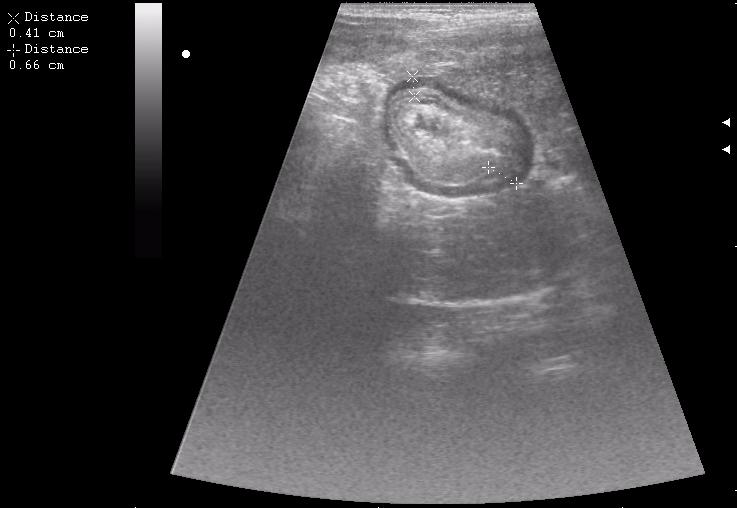

конец рабочего дня тоже "порадовал". Травма об руль велосипеда.

30 мин. после травмы

По поводу "разможжения" ткани паренхиматозного органа при травме. Скорее всего-это участки попитывания кровью,т.н. имбибиция.